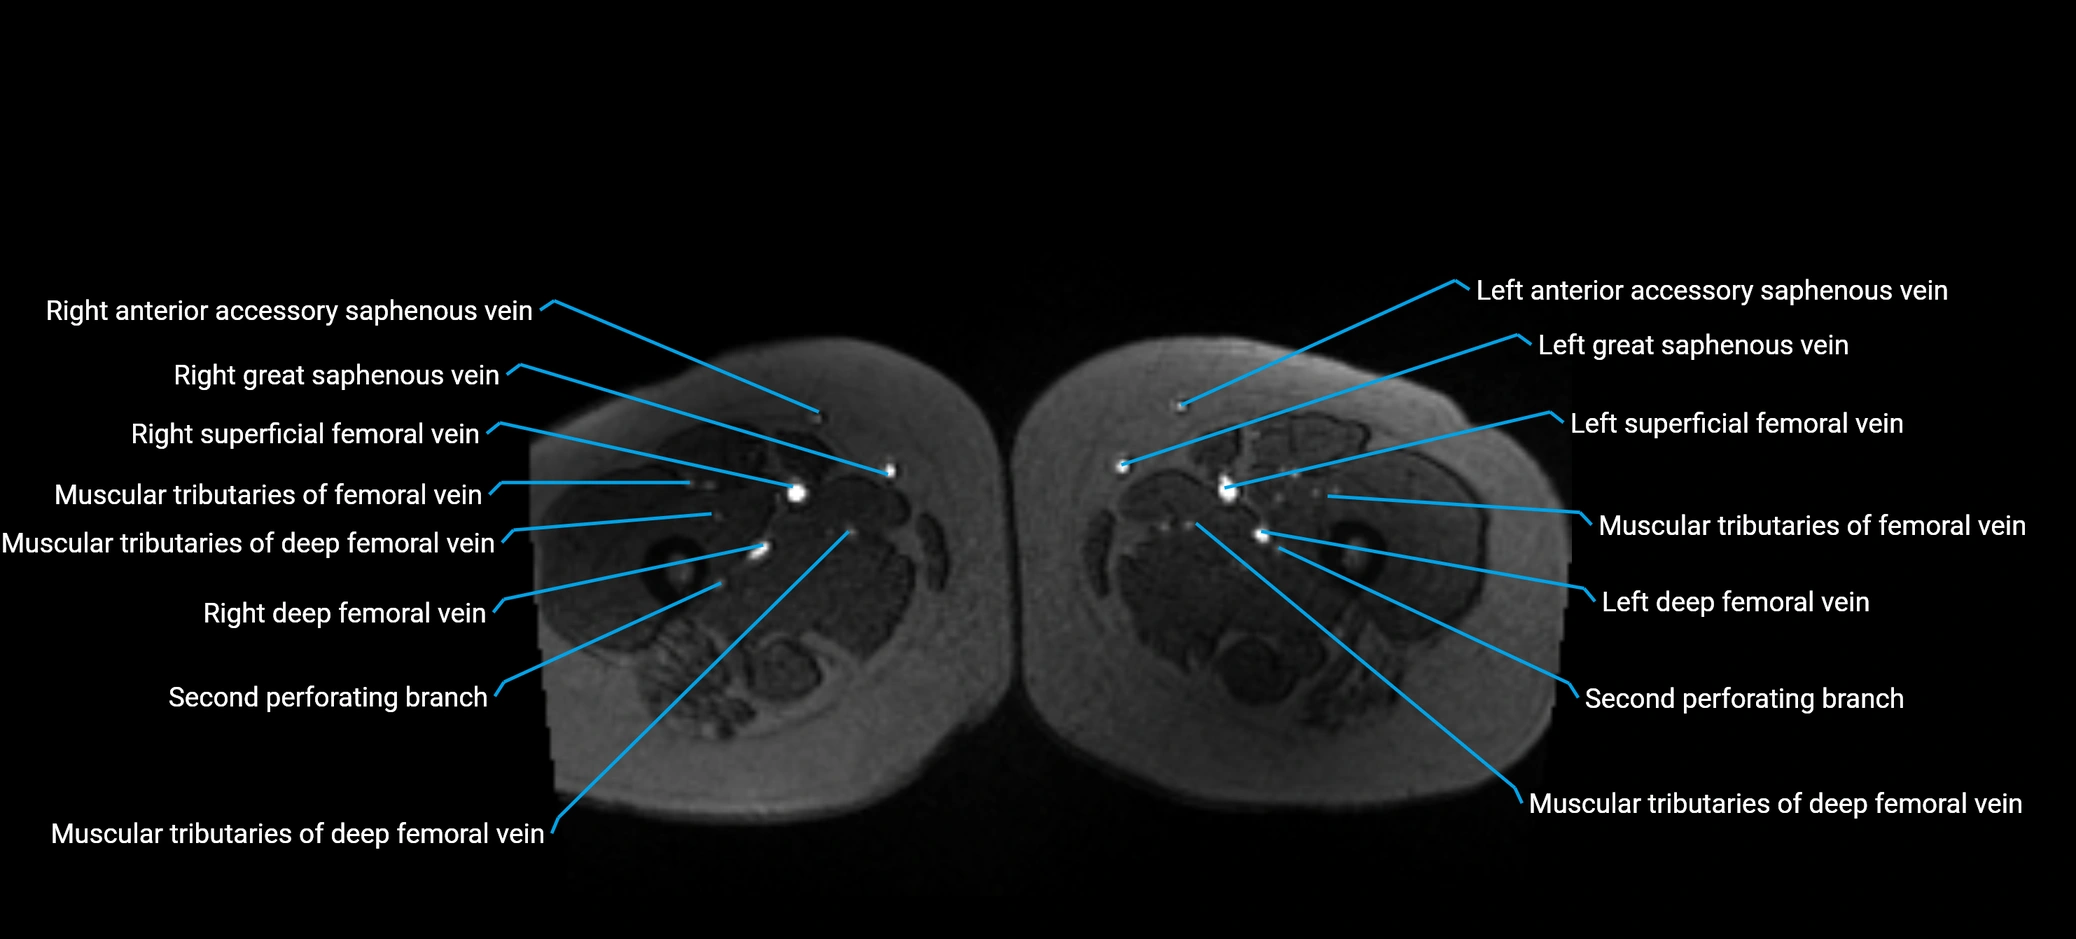

image